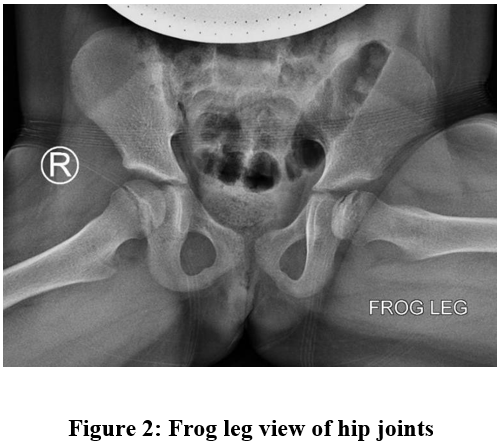

The diagnosis of LCPD was established based on history, physical examination, and x-ray radiograph (Figures 1 and 2) that clearly depicted the advanced features of the disease. The parents were reassured and sent home with an analgesia prescription. The hip pain and limp resolved spontaneously in a short period. A follow up appointment with the patient was scheduled for later, but her parents deferred to present due to COVID-19 related restrictions. The patient is currently asymptomatic and abiding by our medical advice to restrict physical activity. We plan to refer the patient for an MRI examination should symptoms arise again.

Figure 2, Frog leg view depicts a lateral subchondral fracture (Gage sign) running across the left femoral head.